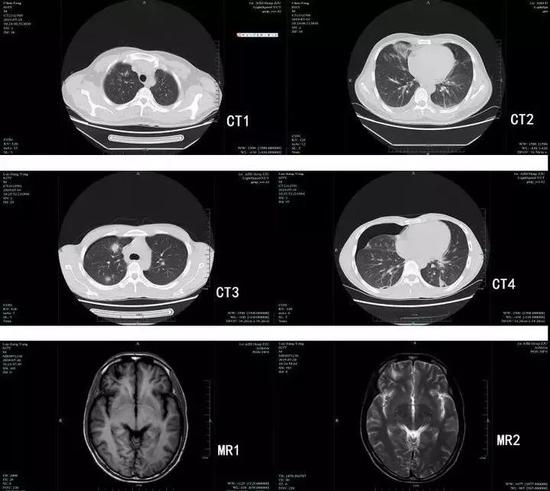

肺吸虫感染后的肺部团块影和颅内软化灶

果然,经过寄生虫检测,两人均为卫氏肺吸虫抗体阳性,均在腹部和肺部发现肺吸虫,骆某更是在脑子里发现肺吸虫囊性灶,比较严重。幸好两人发现及时,并且就医及时,经过药物治疗后康复出院,没有留下后遗症。